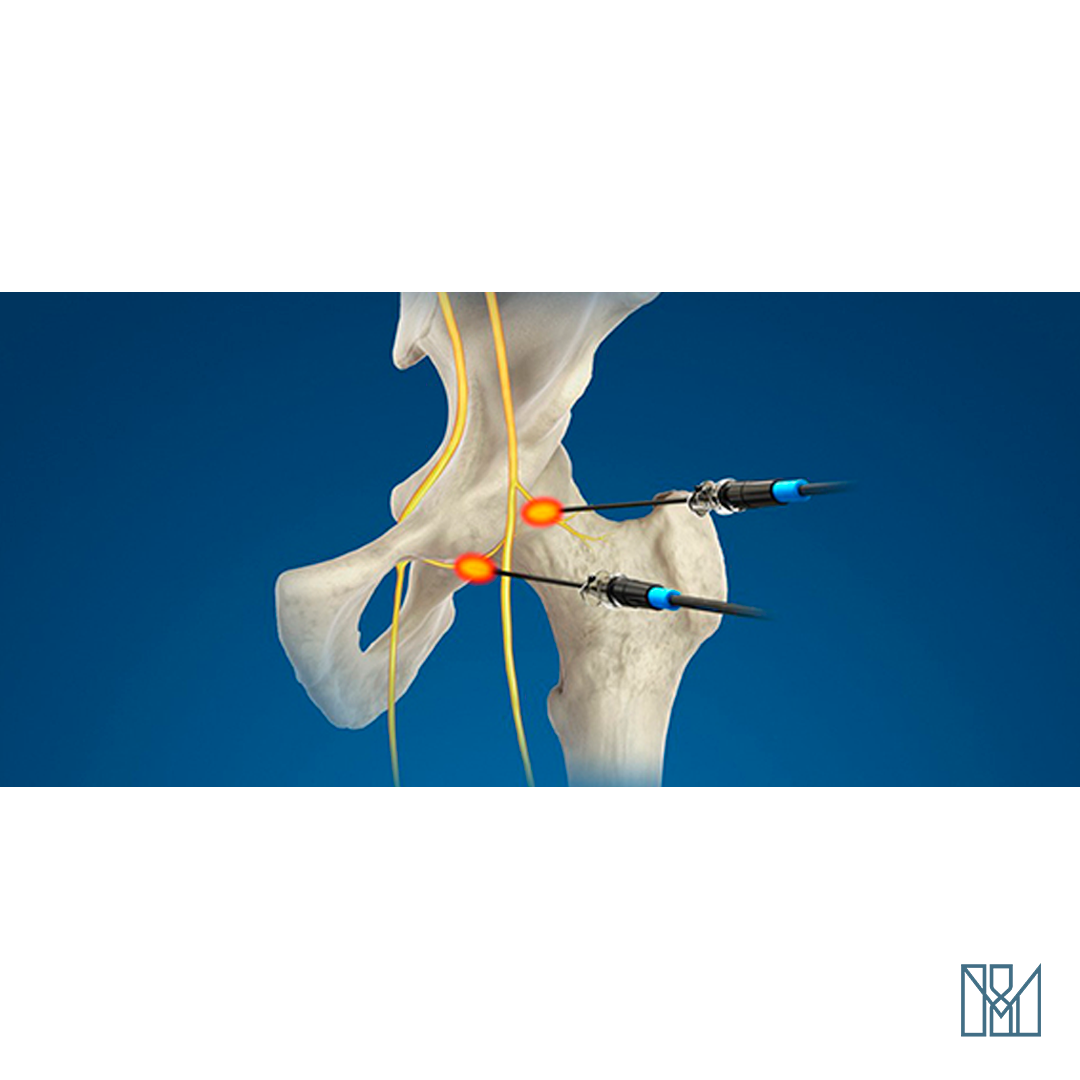

Cânula é um tubo pequeno produzido em materiais como polímero, borracha ou metal, possui calibre mudável, vários formatos e destina-se a diversos objetivos. Pode ser feito de um material rígido ou semirrígido, e as suas extremidades são abertas. É indicada para ser inserida no corpo (em orifício ou em algum órgão) para injetar medicamento ou aspirar material.

A cânula para tratamento de dor é um acessório, assim como o conjunto completo de eletrodos. Esses acessórios são usados em casos de termocoagulação, por exemplo, que necessitam usar a cânula descartável para tratamento de dor.